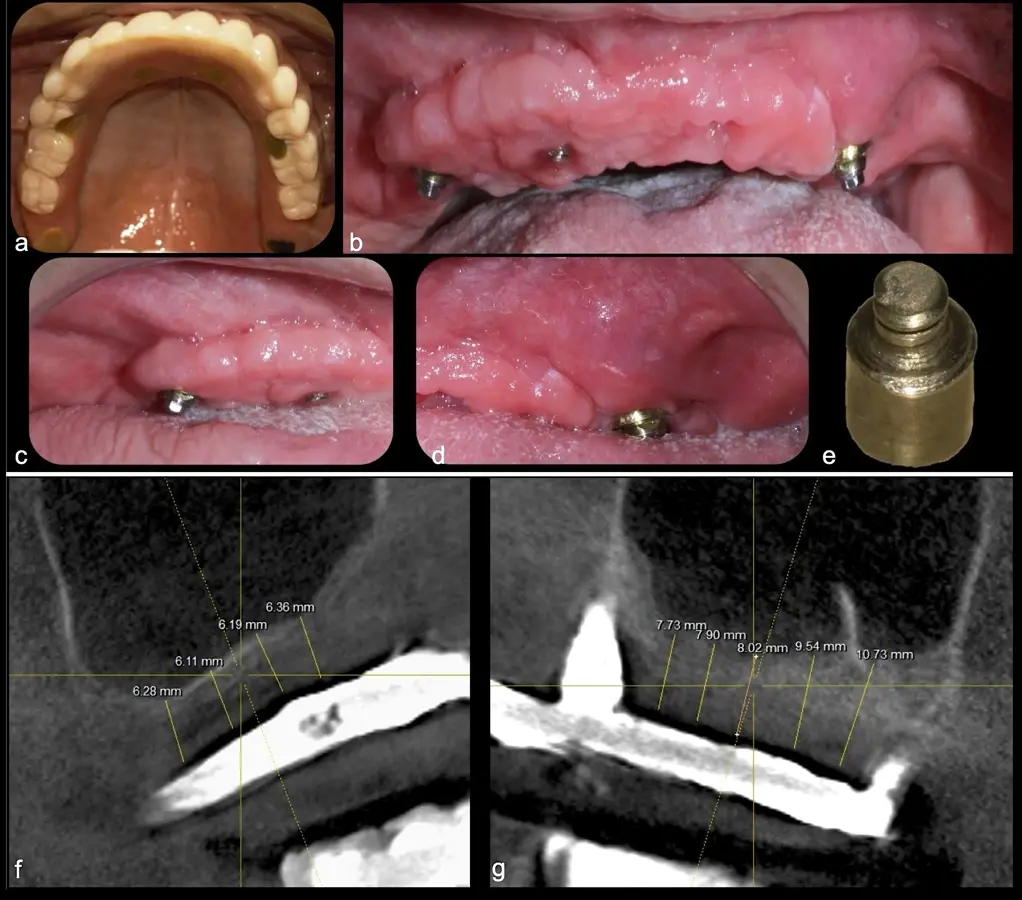

El levantamiento de piso de seno maxilar es una técnica quirúrgica aceptada previa o simultáneamente a la colocación de implantes dentales. La mayor evidencia científica refiere que si se tiene entre 0 -7 mm de altura ósea se debe realizar la elevación sinusal junto con injertos óseos; y a partir de los 8 mm, se hace más predecible la colocación simultánea de implantes dentales.1-3

Aunque esta técnica es predecible, la perforación de la membrana sinusal es la complicación intraoperatoria más común, con una prevalencia de hasta el 58.3%.4 Existen también otras complicaciones reportadas, como hemorragias asociadas a la lesión de la anastomosis arterial en el área de la pared lateral del seno maxilar.5-8

La técnica se inicia con la colocación de anestesia infiltrativa, posteriormente se realiza una incisión crestal o paracrestal con posibles liberantes verticales que deben de estar alejadas por lo menos 5 mm de los límites de la futura ventana y sobrepasar la línea mucogingival. Se realiza una elevación de colgajo, se inicia la antrostomía y antroplastía. Para ello, se emplea el inserto redondo diamantado de corte al momento de delimitar los bordes de la ventana de acceso. Luego se cambia al inserto aserrado liso de calibre fino con superficie diamantada, para profundizar y eliminar el hueso en el contorno de la ventana. Una vez que se traslucen los tejidos, se puede optar por el retiro de la tapa ósea o el levantamiento de ésta junto con la membrana.

El tipo de inserto a ser utilizado dependerá del espesor de la pared ósea. Si la pared es menor a 0.5 mm, es mejor utilizar insertos de desgaste para prevenir la ruptura de la membrana de Schneider; si el espesor es mayor a 0.5 mm, se puede utilizar insertos de corte de espesor medio (Figura 3).

El clínico puede retirar la tabla ósea o introducirla como “tienda de campaña” dentro del seno maxilar. En cualquiera de las alternativas, es importante evaluar la presencia de tabiques óseos y de la arteria postero alveolar superior.